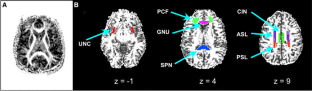

Fig. 1